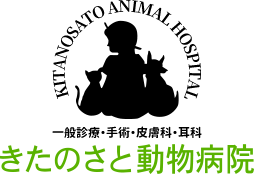

右側の写真が肥大型心筋症で左心室の容量が小さくなってしまったねこちゃんのエコー検査の画像です。オレンジの枠線で囲った部分の大きさが左の写真に比べて小さいのがわかるでしょうか。